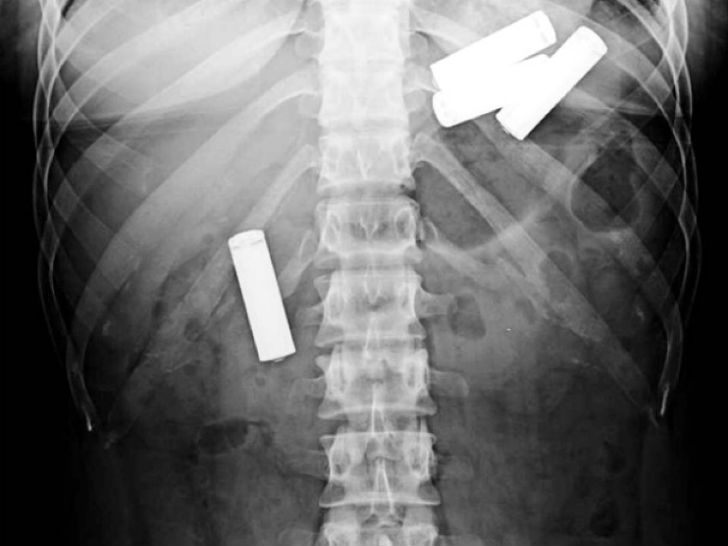

Вот батарейки, пожалуй, глотают только дети. Рентгеновский снимок 13-месячного малыша.